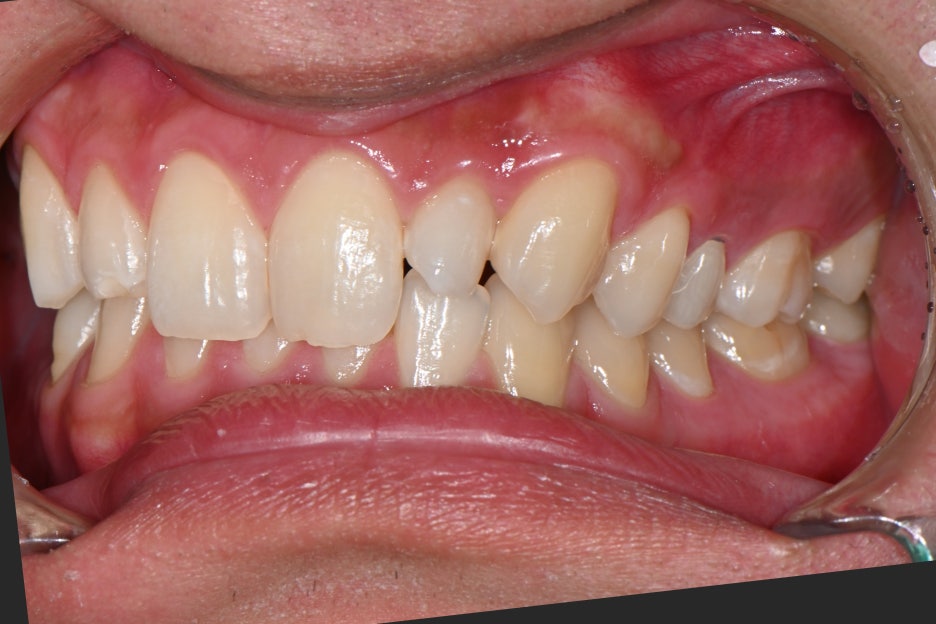

The patient initially visited the hospital for a whitening event.

After three sessions of professional whitening to brighten the overall tone,

an Object Zero Laminate plan was established on top of that.

< Before whitening: A3 > After whitening: A1 >

Before whitening, the tooth color was somewhat dark at an A3 tone,

and after whitening, it became clearly brighter.

The reason this process is important is

to make the color of the Object Zero Laminate

match the adjacent teeth naturally.